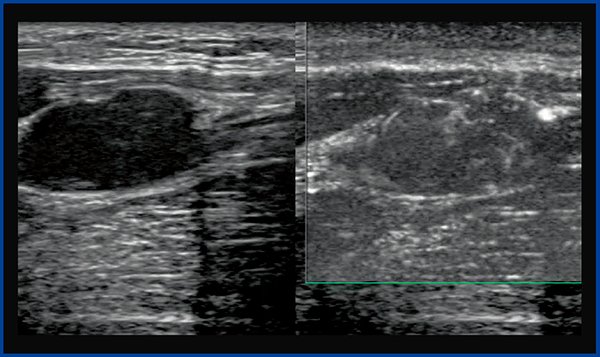

●症例3:神経鞘腫

症例3は,正中神経に発生した神経鞘腫で,カラードプラ(図8)では腫瘍の辺縁と一部の内部に動脈性の速い血流が認められた。内部にはあまり血流がないように思われるが,SMI(図9)では淡い血流が腫瘍内部に認められ,遅い血流があることがわかる。

従来のカラードプラやパワードプラ,ADFでは見えなかった血流がSMIで見えるようになることで,これまでは観察できなかった異常な血流の評価が可能になれば,腫瘍の鑑別や治療方針が変わることも十分考えられる。

なお,SMIはカラーモードに加え,より詳細な観察が可能なモノクロモードもあり,遅い血流の評価に有用である(図10)。

図8 症例3:神経鞘腫のカラードプラ画像

腫瘍の辺縁と一部の内部に動脈性の速い血流を認める。

図9 症例3のSMI画像

腫瘍内部に遅い血流を認める。

図10 SMIのモノクロモード画像(右)